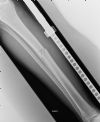

AP Radiograph - Expert Tibial Nail through a distal tibial fracture